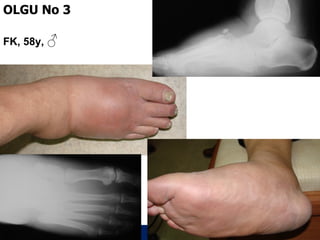

OLGU No 3

FK, 58y, ♂

2,5 ay sonra